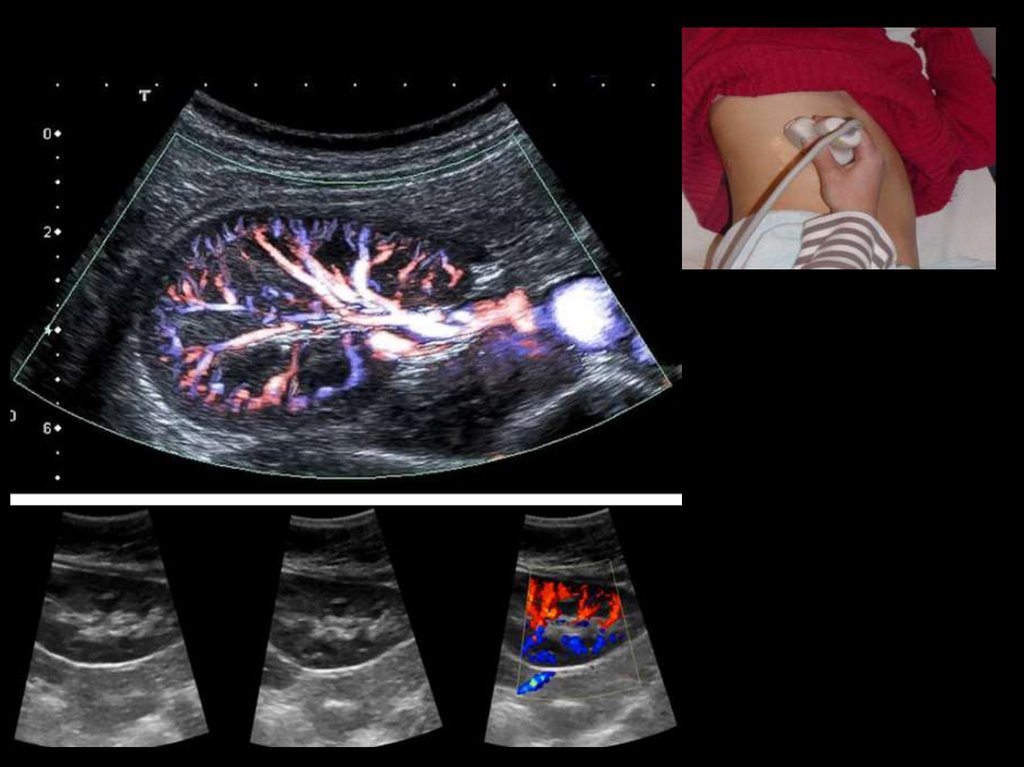

УЗИ КРОВОТОКА ПОЧЕК

• Основной ствол почечной артерии, сегментарные, междолевые и

дуговые

артерии

визуализируются

в

режимецветного

допплеровского картирования

• В режиме энергетического допплера получают отображение еще

более мелкие ин-трапаренхиматозные кровеносные сосуды почек

• Трехмерные

реконструкции

дают

пространственное

представление обо всей сосудистой системе почек.

• Состояние кровотока в сосудах почки

использованием импульсной допплерографии.

оценивается

с